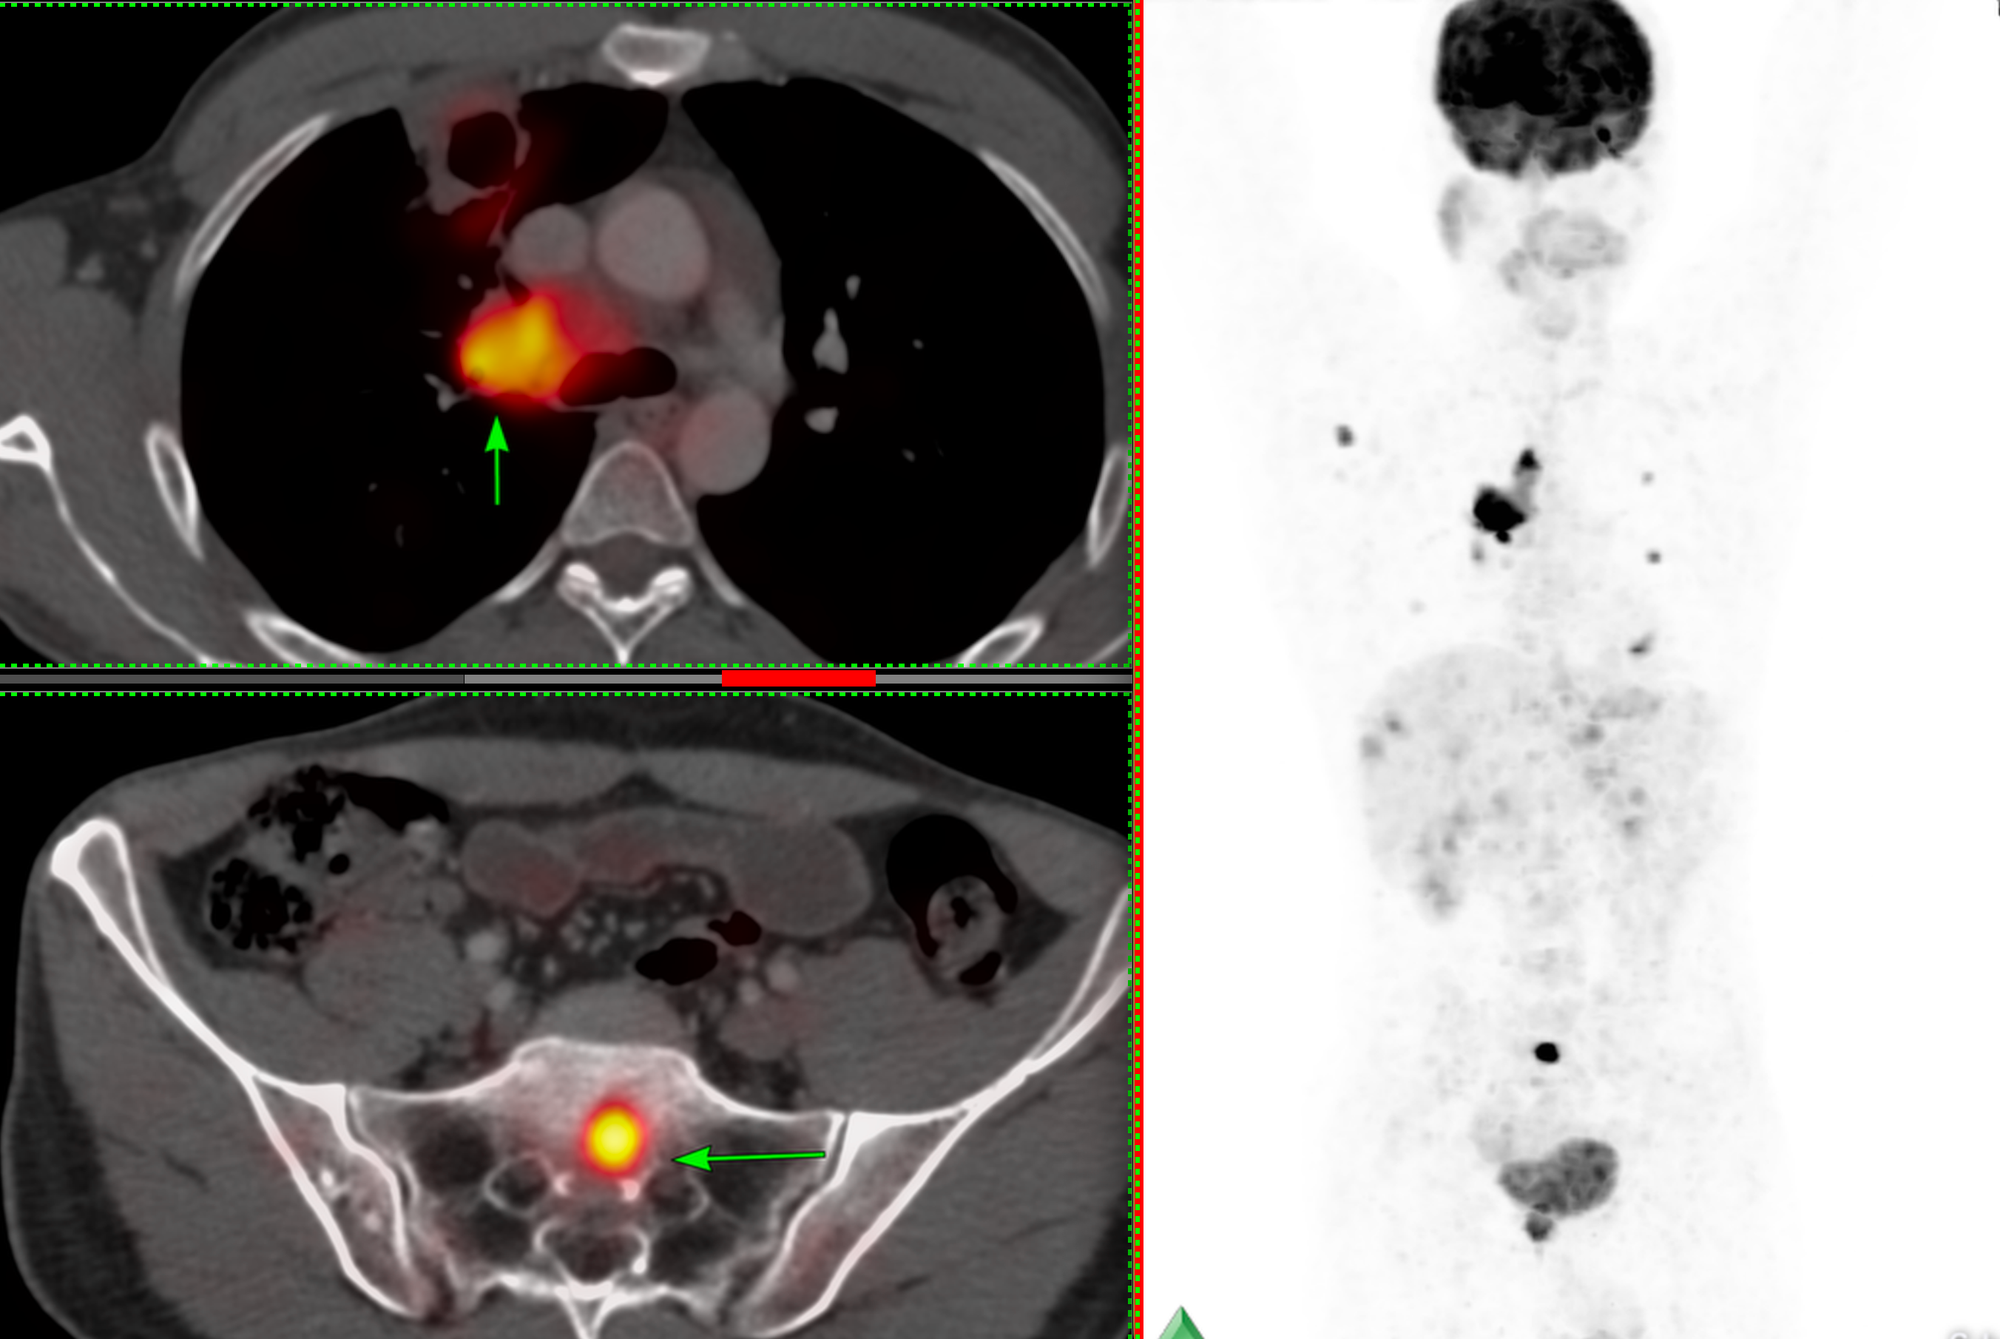

43-years old treated buccal ca had progressive lung and nodal lesions (arrow in to panel), stable liver lesions and a new S1 osteolytic lesion on PET (arrow in bottom panel) (Fig. 1).

The patient was referred for a CT guided biopsy of the sacral lesion.